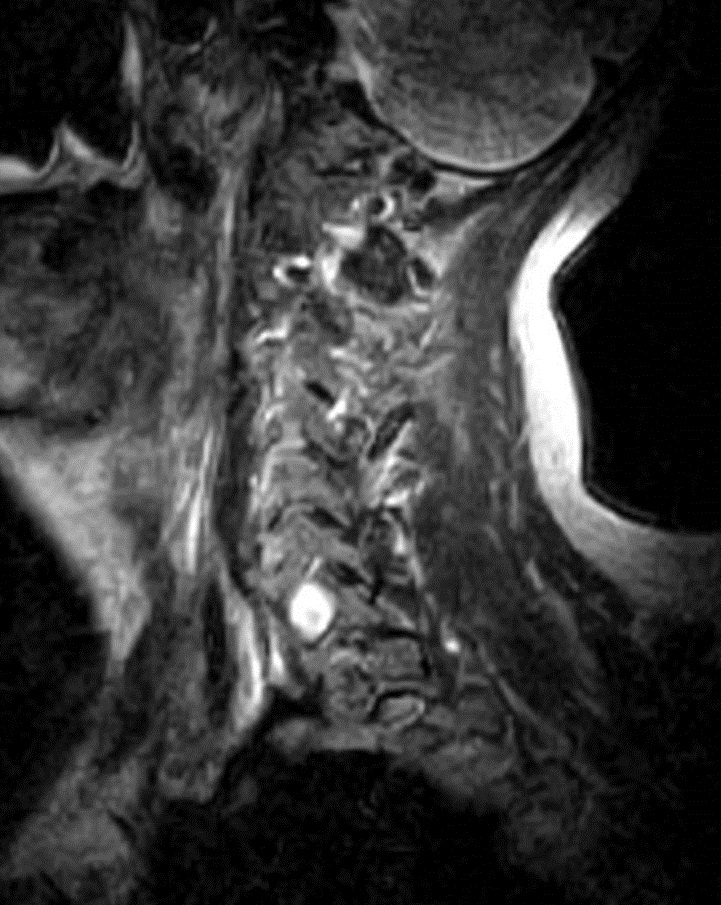

I have provided some select images from the MRI study that was obtained. Initially, the study was ordered non-contrast. Fig. 1 is a midline T-2 weighted image. It demonstrates a degree of posterior disc bulging at C6-C7. No focal posterior discal prominence was noted that would indicate a herniation. Fig. 2 is a gradient echo weighted image through the C6-C7 disc space. In this image, there is obvious expansion of the left intervertebral foramen with a degree of erosion of the facet at the posterior margin of the foramen. The signal intensity is bright on this image, compared to the normal intermediate signal intensity noted within the right foramen. You will note a degree of irregularity at the posterior margin of the disc in this cut, consistent with the disc bulging seen on the sagittal images. There is not sufficient encroachment of the central canal however to account for a neurologic deficit. A left parasagittal STIR image (Fig.3) reveals an obvious focus of abnormal signal within the left C6-C7 IVF that corresponds to the finding that was noted on the axial image. The signal intensity of this area was high on the STIR, gradient echo, and T-2 weighted images, and low on the T1 weighted images, consistent with fluid. At this point what diagnoses would you entertain, and would you order any follow-up imaging or testing?